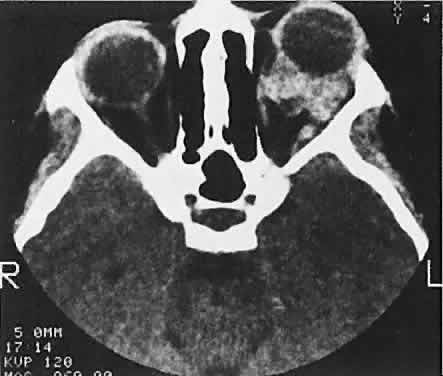

Orbital myositis may represent a greater proportion of cases of IIPT in childhood than in adulthood, and involvement of multiple extraocular muscles may occur more frequently in children than inadults. In orbital myositis, early diplopia and increased discomfort with attempted eye movement are typical symptoms. CT may show enlargement of one or more extraocular muscles in one or both orbits (Figs. 21 and 22). When a single muscle is involved, the specter of a primary or metastatic neoplasm within the muscle may be raised. However, external inflammatory signs, considerable pain and limited motility, and an explosive onset of symptoms within 24 hours all suggest orbital myositis. The uniform enlargement of the muscle, including its tendinous insertion (see Fig. 22), also helps distinguish the process from a neoplasm, which might be expected to produce a more focal, globular expansion. Echography may support the diagnosis of inflammation by showing edema in the episcleral space as a relative sonolucency between the scleral and orbital fat echoes (Fig. 23). Its CT counterpart is an increase in the radiodensity and thickness of the ocular tunica.

Fig. 21. A. This 16-year-old boy had acute onset of bilateral proptosis, pain, diplopia, chemosis, and conjunctival injection. B. Bilateral enlargement of the superior and medial rectus and inferior oblique muscles. Other sections showed similar involvement of other extraocular muscles.

Fig. 22. The uniform enlargement of the left medial rectus muscle, including its tendinous insertion, is characteristic of orbital myositis.